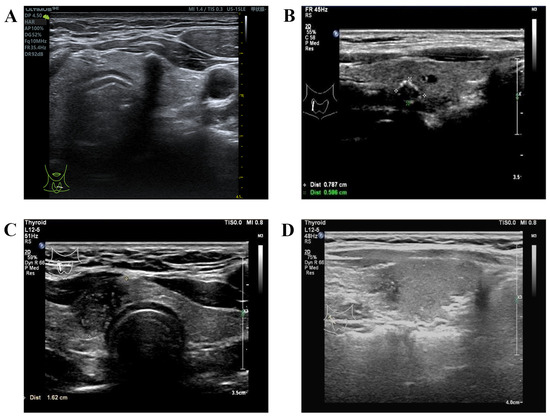

- Li, T.; Li, H.; Xue, J.; Miao, J.; Kang, C. Shear wave elastography combined with gray-scale ultrasound for predicting central lymph node metastasis of papillary thyroid carcinoma. Surg. Oncol. 2021, 36, 1–6. [Google Scholar] [CrossRef] [PubMed]

- Park, A.Y.; Kim, J.A.; Son, E.J.; Youk, J.H. Shear-Wave Elastography for Papillary Thyroid Carcinoma can Improve Prediction of Cervical Lymph Node Metastasis. Ann. Surg. Oncol. 2016, 23 (Suppl. 5), 722–729. [Google Scholar] [CrossRef] [PubMed]

- Zhong, L.; Xie, J.; Shi, L.; Gu, L.; Bai, W. Nomogram based on preoperative conventional ultrasound and shear wave velocity for predicting central lymph node metastasis in papillary thyroid carcinoma. Clin. Hemorheol. Microcirc. 2023, 83, 129–136. [Google Scholar] [CrossRef] [PubMed]

- Han, D.Y.; Sohn, Y.M.; Seo, M.; Yun, S.J.; Park, W.S.; Jeon, S.H.; Cho, Y.H. Shear-wave elastography in thyroid ultrasound: Can be a predictor of extrathyroidal extension and cervical lymph node metastasis in papillary thyroid carcinoma? Medicine 2020, 99, e23654. [Google Scholar] [CrossRef] [PubMed]